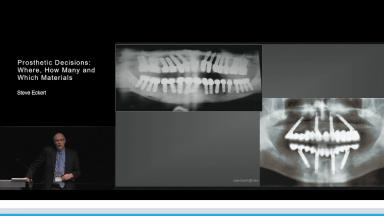

Implant dentistry began with the notion that dental implants should replace the roots of natural teeth. This was frequently interpreted as a one for one replacement whereby one implant would be used to replace one tooth.

Over time this ratio was rejected. Today there is strong evidence to suggest that the minimum number of implants necessary to retain a dental prosthesis may be appreciably less than what was previously thought.

When considering fixed dental prostheses in the mandible there is strong evidence to suggest that three implants could be used with a high level of predictability. In the maxilla four implants might be a more appropriate minimum number.

Although it is appealing to establish a set of minimum numbers, clinicians must be constantly be aware that in some situations minimum numbers are clearly inappropriate.

Likewise it is incumbent upon the clinician to understand that the materials that are considered for the permanent prosthesis must be matched to the number of implants and the associated inter-implant spans.